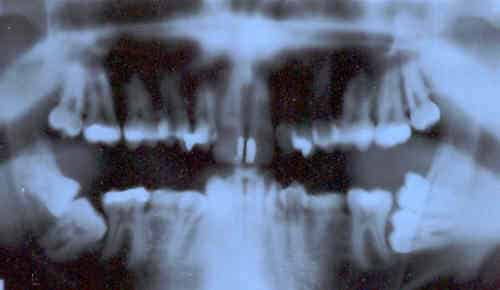

Depuis quelques années, plusieurs enquêtes ont alimenté le débat, en démontrant que la part des prothèses dentaires importées à bas coûts de pays “émergeants” comme la Chine ou Madagascar était en constante augmentation, sans que l’économie importante réalisée ne soit répercutée sur la facture finale.

La loi de 2010 obligeait le professionnel à mentionner le prix d’achat des prothèse sur son devis, avec pour objectif de favoriser la concurrence et freiner l’augmentation des prix. Insupportable pour les organisations professionnelles qui ont finalement obtenu gain de cause auprès du ministre Xavier Bertrand.

Selon une étude de l’Institut de rechercheet documentation en économie de la santé (IRDES), le renoncement à des soins dentaires concerne 10,7 % de la population